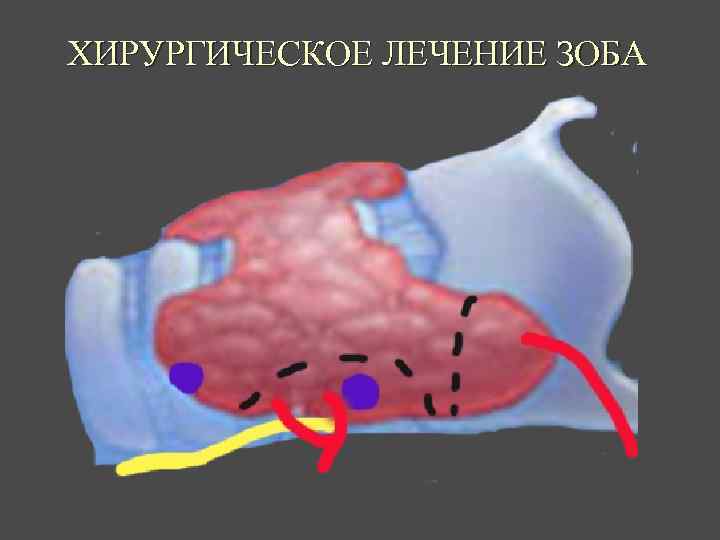

ХИРУРГИЧЕСКОЕ ЛЕЧЕНИЕ ЗОБА

ОСЛОЖНЕНИЯ ХИРУРГИЧЕСКОГО ЛЕЧЕНИЯ ►Поражение возвратного нерва, приводящее к параличу голосовой связки на стороне поражения, как следствие – изменение тембра голоса, сужение голосовой щели, затруднение дыхания. ► Кровотечение. ►Тиреотоксический криз. ► Гипопаратиреоз. ► Рецидив тиреотоксикоза. ► Формирование порочного рубца.